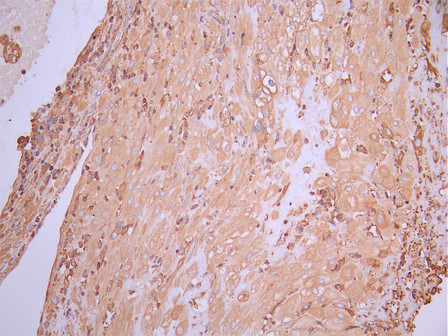

• IHC image of CSB-RA150297A0HU diluted at 1:100 and staining in paraffin-embedded human placenta tissue performed on a Leica BondTM system. After dewaxing and hydration, antigen retrieval was mediated by high pressure in a citrate buffer (pH 6.0). Section was blocked with 10% normal goat serum 30min at RT. Then primary antibody (1% BSA) was incubated at 4°C overnight. The primary is detected by a Goat anti-rabbit polymer IgG labeled by HRP and visualized using 0.05% DAB.

• IHC image of CSB-RA150297A0HU diluted at 1:100 and staining in paraffin-embedded human colorectal cancer performed on a Leica BondTM system. After dewaxing and hydration, antigen retrieval was mediated by high pressure in a citrate buffer (pH 6.0). Section was blocked with 10% normal goat serum 30min at RT. Then primary antibody (1% BSA) was incubated at 4°C overnight. The primary is detected by a Goat anti-rabbit polymer IgG labeled by HRP and visualized using 0.05% DAB.